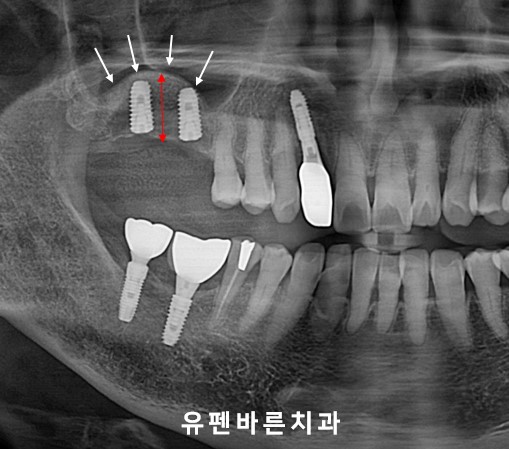

(두번째 케이스)

위 환자분의 경우에도

어금니가 상실되고

상악동 막이 아래쪽으로 내려오면서

임플란트를 식립하기에

뼈높이가 많이

부족한 상태셨습니다. ㅠ.ㅠ

눈으로만 봐도 잔존뼈 높이는

2-3mm정도밖에 되보이지 않습니다.

상악동 거상 과

충분한 양의 뼈이식을 통해

잠실새내임플란트 식립을

잘 마치셨는데요 :)

반구형 모양의

동그랗게 뼈이식이

예쁘게 된 모습이

보이시나요? ㅎㅎ

Sinus Augmentation Teeth No. 13,14,15

As always,

원장님은

수술 중에

3D CT를 통해

상악동막이 찢기지는 않았는지,

뼈이식 양과 높이는 제대로 올라가는지

꼭 체크합니다. :)